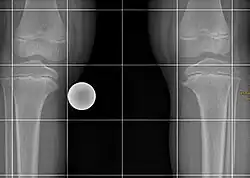

Röntgenbild eines 5½-jährigen Mädchens mit beidseitigem Morbus Blount Stadium II

Nach Langeskjöld[2] können verschiedene prognose- und therapierelevante Stadien unterschieden werden:

• Stadium I: Varusdeformität mit Unregelmäßigkeit der Wachstumsfuge und medialseitiger Hakenbildung

• Stadium II: Absenkung der Tibiametaphyse medial mit leichter Schrägstellung

• Stadium III: Deutliches Varus und ausgeprägter Haken medial, eventuell Fragmentierung der Metaphyse medial

• Stadium IV: Verschmälerung der Wachstumsfuge mit deutlicher Schrägstellung

• Stadium V: Zusätzliches Deformierung und Teilung der Epiphyse

• Stadium VI: Brückenbildung zwischen Epi- und Metaphyse auch mit teilweiser Fusion der fragmentierten Epiphyse an die Metaphyse medial.